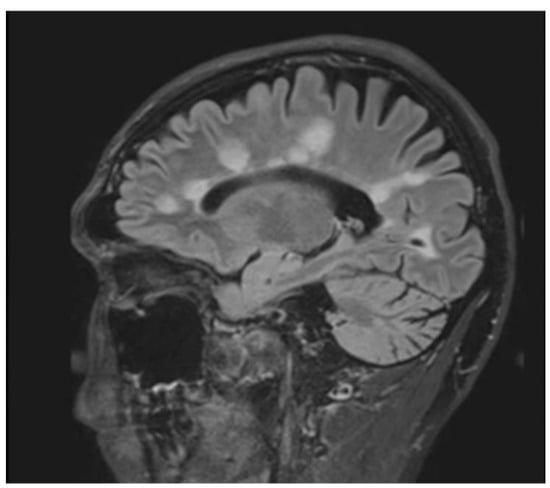

Figure 1.

Sagittal fluid attenuated inversion recovery (FLAIR) image shows lesions perpendicular to lateral ventricle giving classic finger-like appearance, Dawson’s fingers.